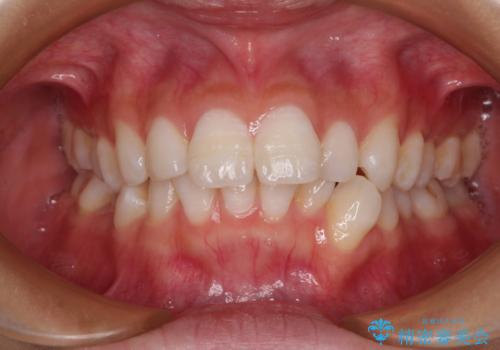

- 口を閉じたときに飛び出してしまう上顎前歯を気にして来院された患者様です。

下顎はデコボコが気になっていたため、上下左右第一小臼歯4本を抜去して、ワイヤー装置にて口元の突出感を改善するよう矯正治療を行うこととしました。

下唇に前歯が当たって跡が残ってしまう状態でしたが、スッキリとした口元に仕上げることができました。